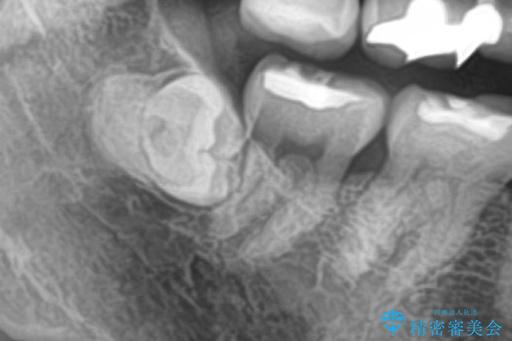

埋伏歯の抜歯

パノラマ,CT撮影を行い安全なことを確認して抜歯を行いました。